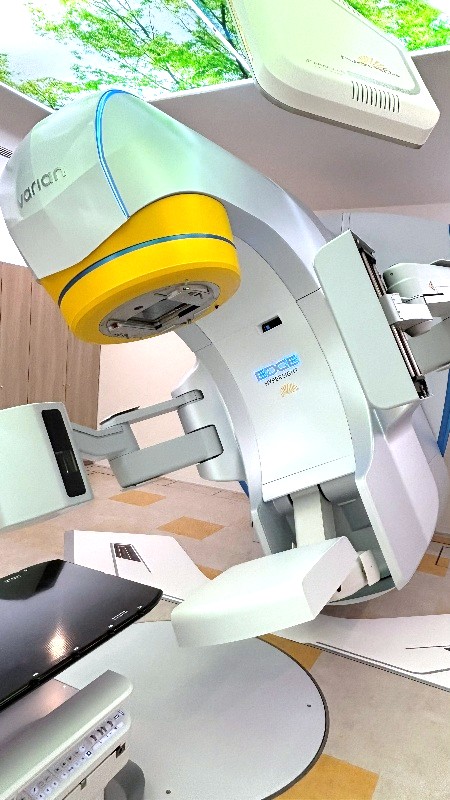

Novalis Edge(正式名称:Novalis powered by TrueBeam Edge HyperSight)は、バリアン社製の高精度リニアック「TrueBeam Edge HyperSight」と、ブレインラボ社製の定位放射線治療用画像誘導システム「Novalis Radiosurgery System」を組み合わせた放射線治療装置です。

TrueBeam Edge HyperSightとは

TrueBeam Edge HyperSight は、高精度な画像誘導や照射制御を活用し、病変に応じた放射線治療を行うための放射線治療装置(医療用リニアック)です。精密な治療計画に基づき、照射範囲や線量分布を適切に設定することで、周囲の正常組織への影響を可能な限り抑えた治療を目指します。

高精度リニアック本体(TrueBeam Edge)

高精度な放射線照射を行うための医療用直線加速器です。高い機械精度と高速な照射制御により、病変の形状に応じた線量分布の形成が可能です。

また、高線量率モードでは、6 MV X線で1,400 MU/分、10 MV X線で2,400 MU/分(通常照射モードでは600 MU/分)といった高速照射が可能であり、特に照射時間が長くなる定位放射線治療に有効です。

さらに、ロールやピッチ方向の補正が可能な PerfectPitch(6軸補正治療寝台)を搭載しており、患者さんの体位を高精度に補正することができます。